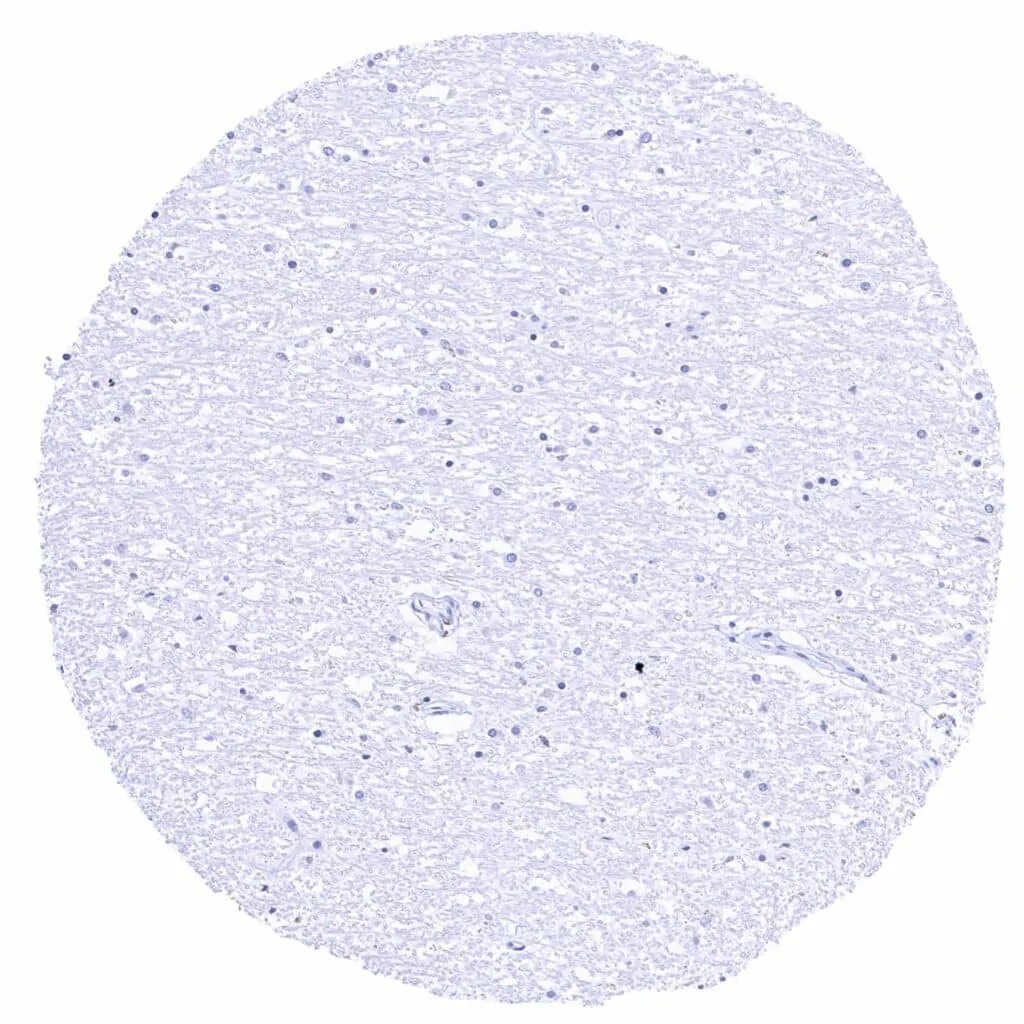

Cerebrum, grey matter

Cerebrum, white matter